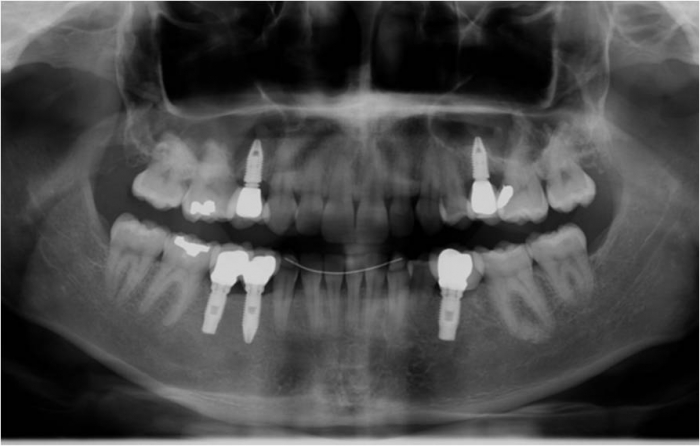

Raio x após dentes provisórios fixos instalados

Raio x final